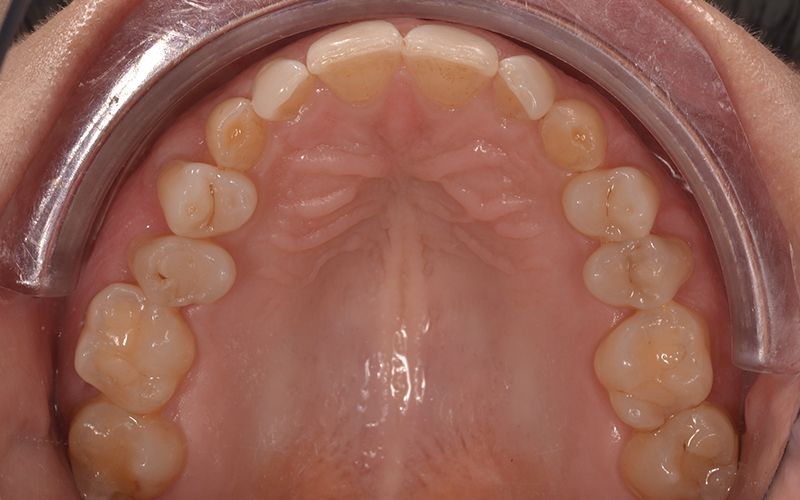

Fruto del trabajo en I+D+I, y de la capacidad productiva en el ámbito de la impresión 3D y de los materiales, en Avinent lanzamos alineadores invisibles personalizados para resolver todos los retos estéticos y funcionales. Recode Aligners, es la marca de alineadores de Avinent, que además de tratar multitud de casos con éxito, ofrece todos los recursos de comunicación para que la clínica pueda llegar a los pacientes. De igual manera, nuestra línea también incorpora otras soluciones ortodónticas como los retenedores y las férulas de descarga.